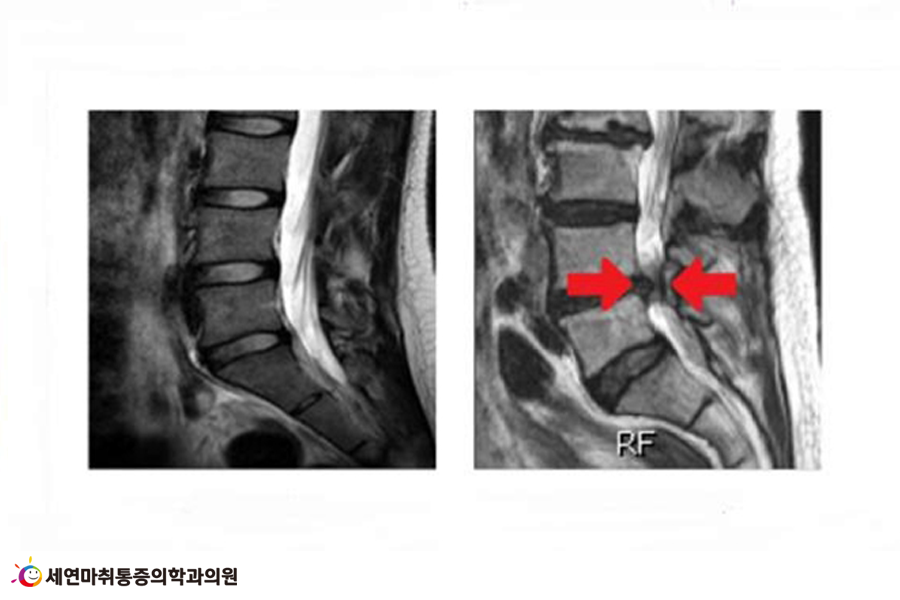

척추관협착증이란 신경근이 나오는 길인 척추관이 퇴행 및 여러 가지 원인으로 인해 좁아져서, 그 부위의 신경근이 압박을 받는 질환입니다. 척추관(척추 신경이 지나가는 공간)이 좁아져서 신경을 누르는 척추신경염증입니다.

나이가 들수록 우리 몸 곳곳에는 이상 변화가 감지되고 서글프지만, 세포도 늙고 피부도 늙고 관절도 늙어가는데요, 노화로 인해 척추뼈도 두꺼워지고 척추 신경을 감싸는 척추관에도 영향을 끼칩니다.

뿐만 아니라 척추관을 둘러싼 수많은 인대와 근육들도 노화로 인해 탄력성이 떨어져, 결국 척추관이 점점 좁아지면서 그 아래 신경근을 눌러 잦은 허리 통증을 유발하게 되는 것이지요.

척추관이 좁아지는 이유는 여러 가지가 있는데, 견고한 골조직으로 둘러싸여 있는 신경조직이 추간판(디스크)의 변성을 부추길 수도 있습니다.

또한 추간 관절의 변화가 생길 수도 있고, 관절돌기의 골극(뼈곁돌기)이 자라서 주변 조직을 자극하기도 합니다.

이 외에도 황색인대가 신경근 쪽으로 퇴화되어 두꺼워지는 등 여러 가지 환경이 척추관을 좁아지게 만들고 신경을 압박해 통증을 유발하게 됩니다.